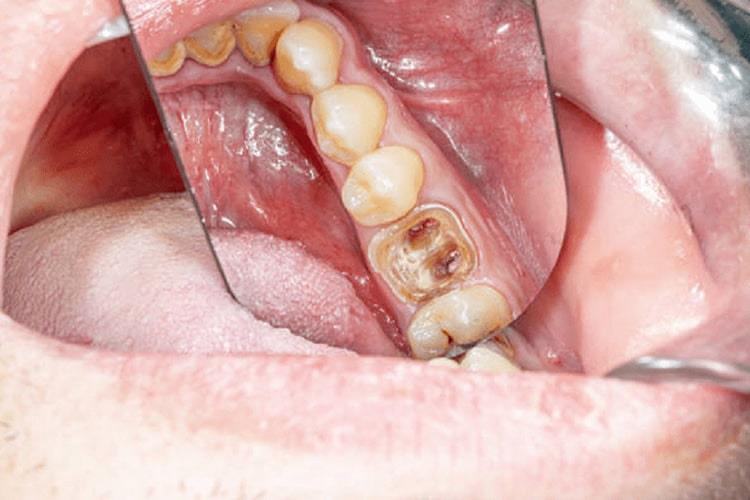

قرار گرفتن پالپ در معرض محیط خارجی

عواملی مانند پوسیدگی و ترکخوردگی میتوانند پالپ دندان را در معرض محیط خارجی و عوامل آسیبرسان قرار دهند که باعث عفونت میشود. در صورت عدم درمان، این عفونت میتواند به سایر بخشهای دهان و بدن گسترش یابد. مراحل پیشرفت عفونت پالپ دندان عبارتاند از:

- ورود باکتریها به پالپ

- التهاب و ایجاد درد دندانی

- مرگ پالپ در صورت عدم درمان

- گسترش عفونت به سایر نواحی مانند فک و سینوسها